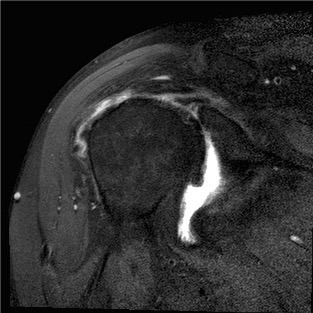

MRI

Rotator cuff tears

MRI with supraspinatus tear, Hill Sachs lesion and significant glenoid bony deficiency